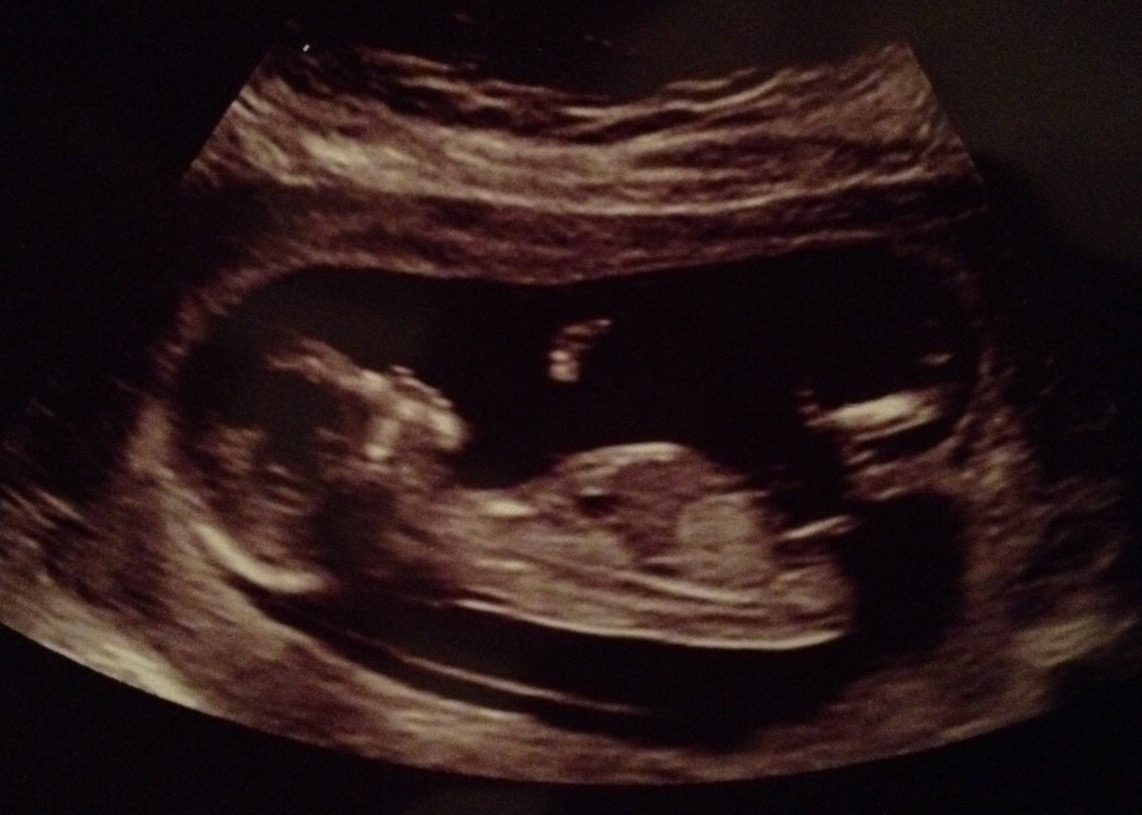

13 weeksAttachment 34479

girl

Very girlie shape but angled at the end, tricky one am giving a slight boy lean but am mot sure x

Saying boy based on angle and potential stacking..

Boy

First time I've ever guessed, looks very similar to my boy nub. So I think boy :)

I am hoping for a girl this time but do you think the nub is angled too far upwards at 13+2 weeks to be a girl? Do you measure the angle of the nub against the lowest part of the spine (that's slightly curved) or the main part of the spine?

Also, is the fork at the end stacking? The line seems to come from underneath the nub, does that mean anything?

I based my guess on the angle, the end looks more forked to me than stacking but angle is definitely more boy. Nubs can be wrong, it could be a girl. I would send pink dust but I don't seem to have any! Good luck x o

Going girl because it's a long long nub and also it goes based on angle of lower spine. I'm pretty sure that's a girl